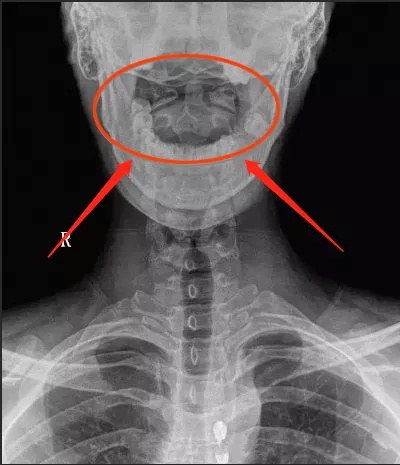

触诊检查发现,她的颈1横突偏歪,X光片显示寰齿侧间隙左右不等宽;颈1、2关节间隙不平行,颈2、5、6棘突偏歪,有压痛。

X光片开口位,寰齿侧间隙不对称

① 开口位片见寰椎双侧的侧块不对称,寰齿侧间隙及寰枢关节间隙左右不对称,枢椎棘突偏歪。